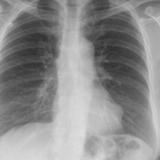

Case 2  Lung cancer and

Peric calcification